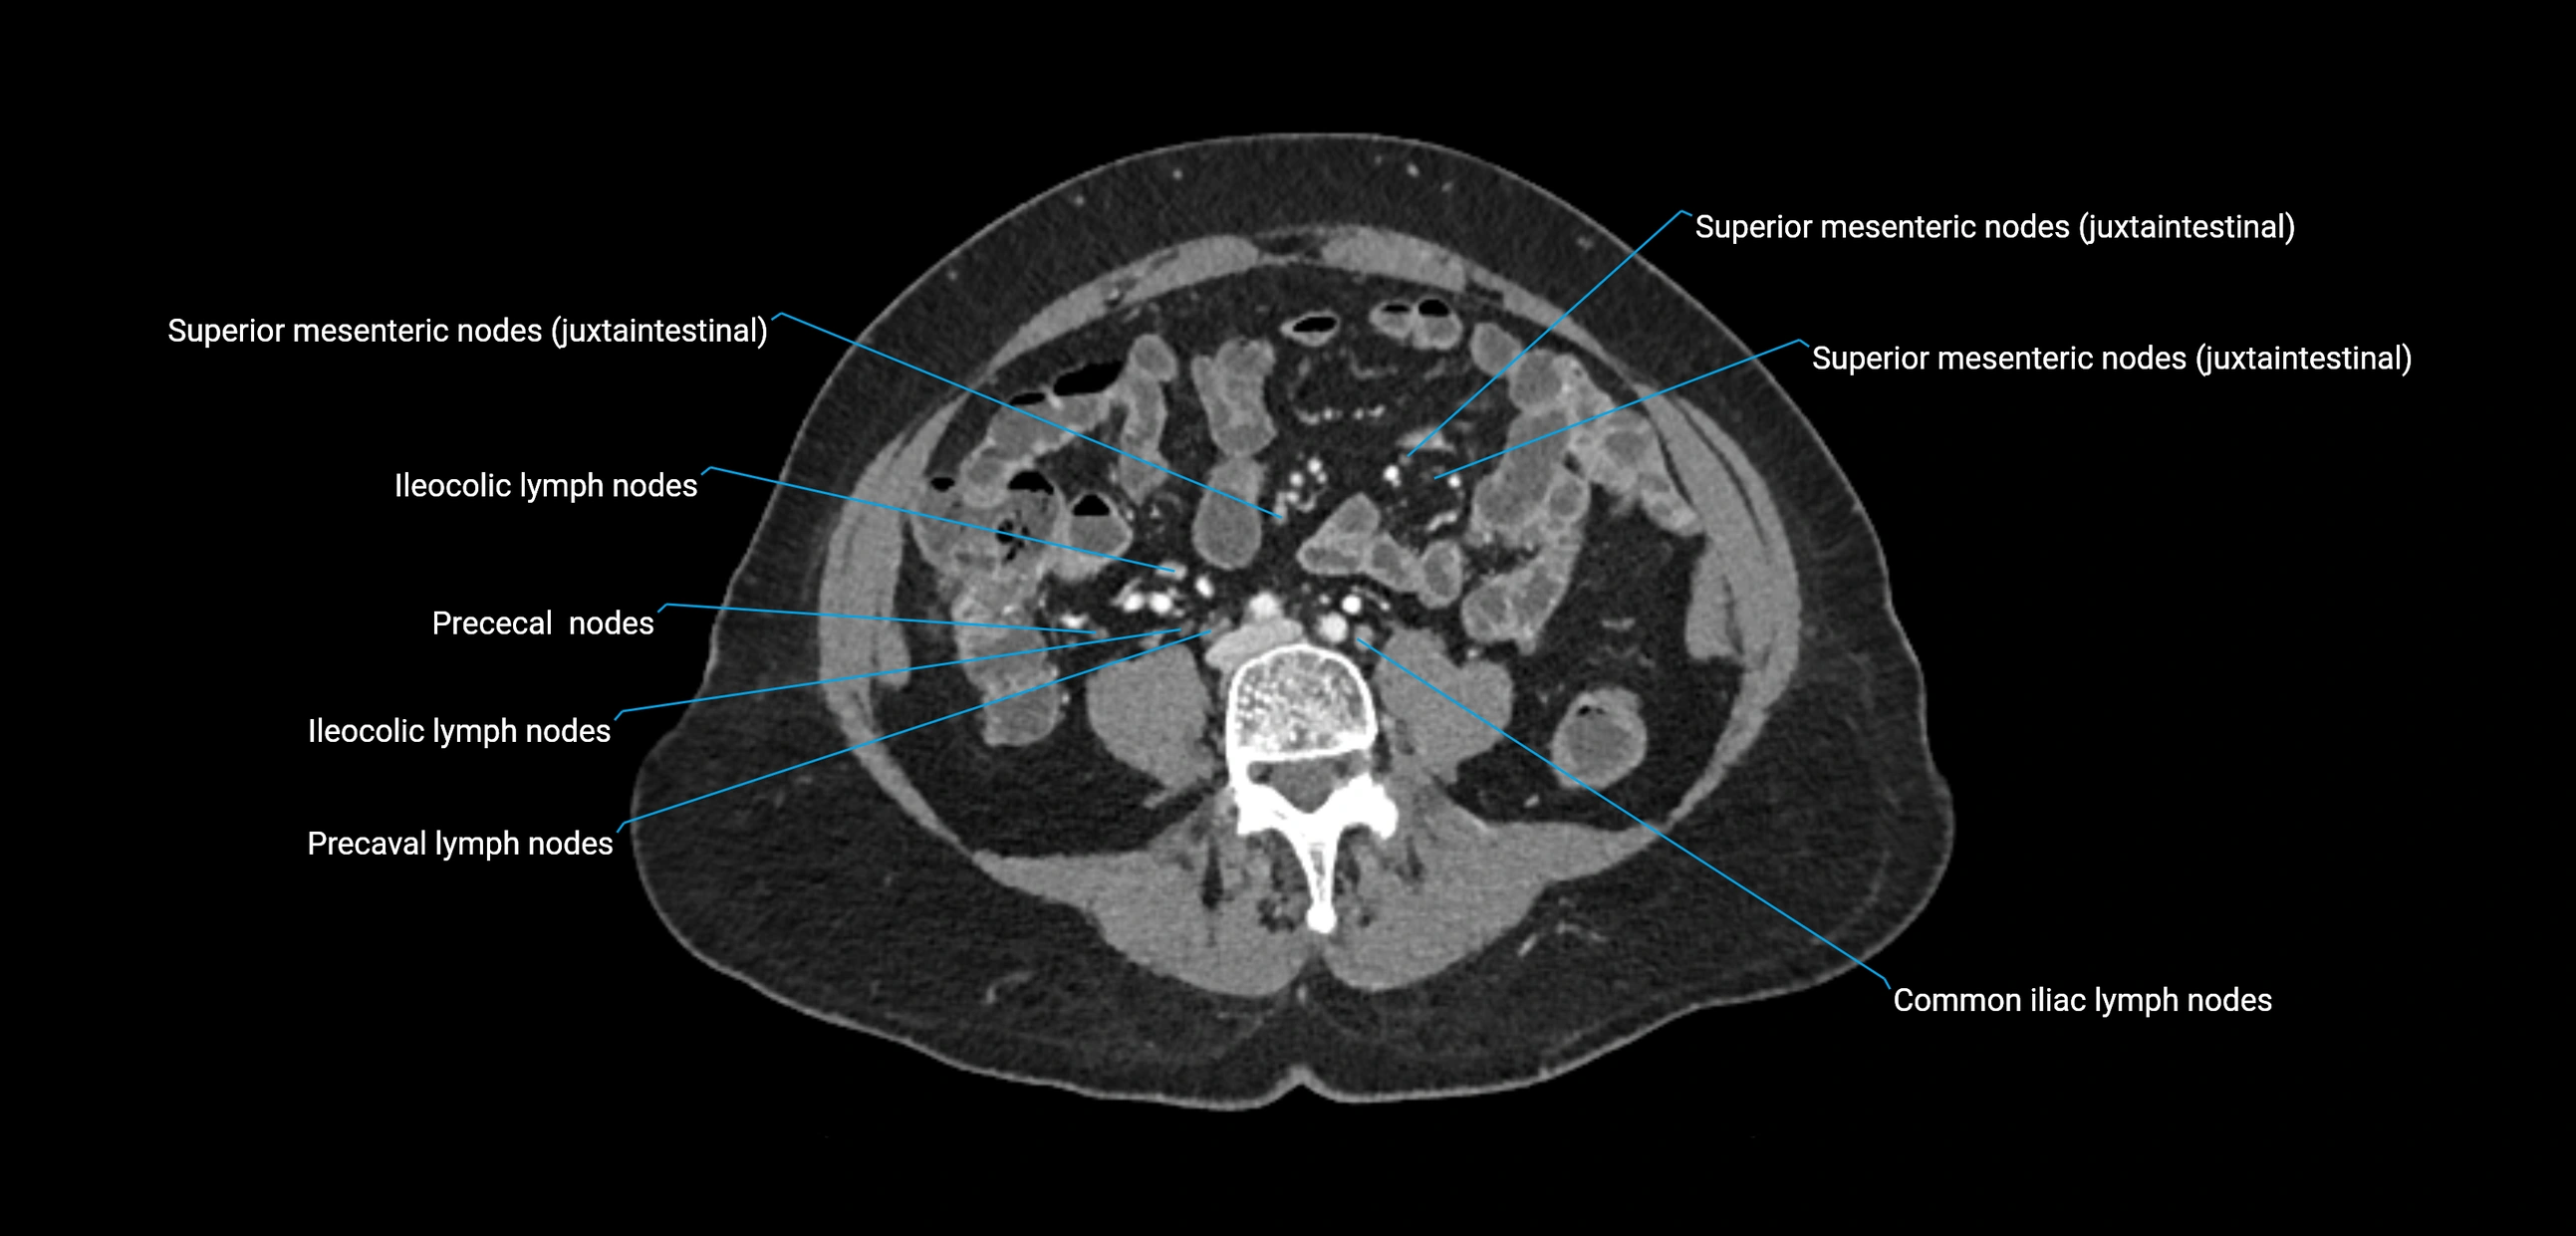

CT Appearance

CT Pre-Contrast:

• Nodes appear as soft-tissue density nodules adjacent to the aorta and IVC

• Calcification may be seen in chronic infections (e.g., tuberculosis)

CT Post-Contrast:

• Normal nodes enhance homogeneously

• Malignant nodes may show heterogeneous enhancement, central necrosis, or conglomerate formation

• Size >1 cm short axis is suspicious, though morphology and distribution are equally important